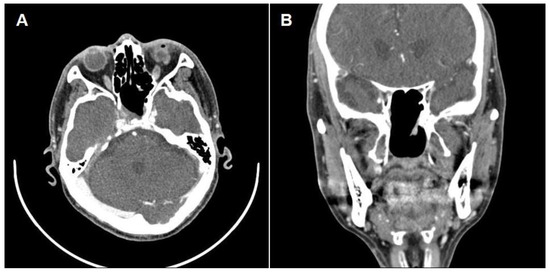

Successful Endoscopic Transsphenoidal Approach Treatment of Sphenoid Sinus Organized Hematoma Causing Visual Deficit: A Case Report

Background: Organized hematoma in the sphenoid sinus is rare, but serious complications, such as visual deficits, can occur. Three such case reports have been published previously in the literature; however, none have achieved complete recovery of the vision. Case presentation: A [...] Read more.

Background: Organized hematoma in the sphenoid sinus is rare, but serious complications, such as visual deficits, can occur. Three such case reports have been published previously in the literature; however, none have achieved complete recovery of the vision. Case presentation: A 69-year-old male patient was referred to the ear, nose, and throat department with an expansile soft tissue mass filling the right sphenoid sinus and blurry vision in his right eye. Complete mass removal was achieved by a wide opening of the sphenoid sinus via an endoscopic transsphenoidal approach, followed by cauterization of the feeding artery and coverage by a nasoseptal flap. The patient’s vision was restored after the operation, and he declared no visual symptoms until the latest follow-up (one year after the surgery). Conclusions: Complete excision with an endoscopic endonasal transsphenoidal approach can restore visual deterioration caused by a sphenoid sinus organized hematoma. Full article